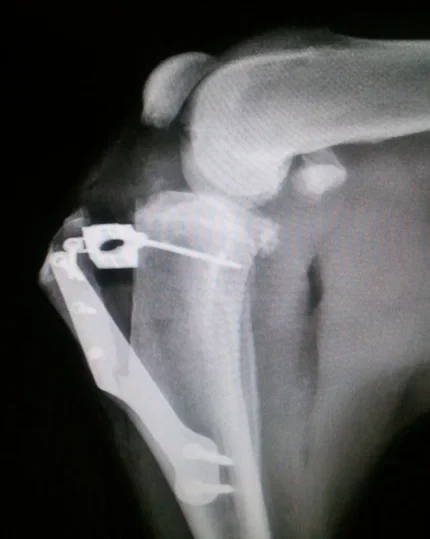

Galería de casos clínicos

Casos clínicos de cirugía (tejidos blandos, traumatología, neurocirugía, artroscopia)